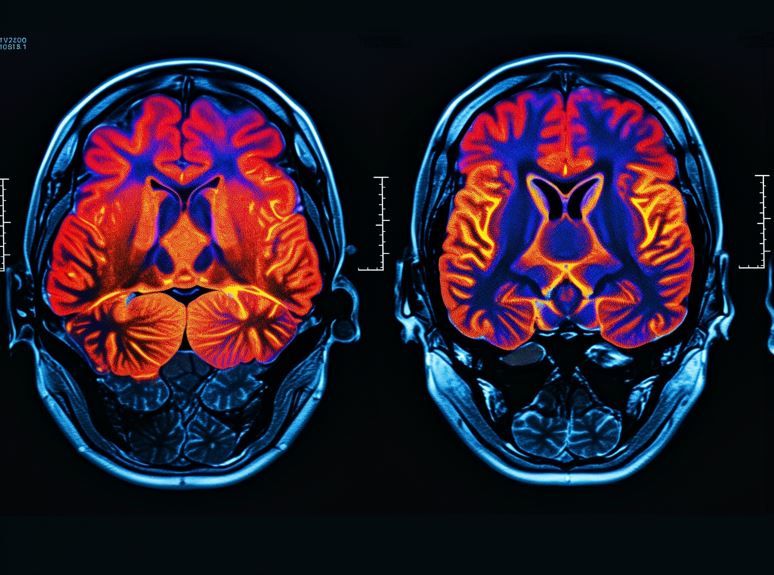

The ReCODE program targets metabolic, infectious, immune, vascular, and toxic exposures, elements that underlie both mood and cognition, study authors said.

ReCODE is a precision medicine protocol developed by Apollo Health and based on the research of Dale Bredesen, MD. Unlike single-target drug therapies, ReCODE uses a multifactorial strategy to identify and address contributors to cognitive decline, including insulin resistance, chronic infections, vascular risk, nutrient deficiencies, toxin exposures, sleep apnea, and chronic stress. Personalized interventions based on individual assessments range from dietary and lifestyle modifications to targeted medical management.1,2

Rao and colleagues pointed out that these same physiologic drivers are also implicated in depression. By systematically correcting metabolic, inflammatory, infectious, immune, and toxic influences, ReCODE may exert parallel benefits on cognition and mood, they suggested.1